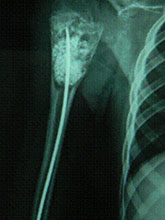

Unicameral Bone Cyst (UBC) or Simple Bone Cyst (SBC)

Unicameral Bone Cyst (UBC) or Simple Bone Cyst (SBC) constitutes 3 % of all bone tumours.

Treatment Modalities

About Bone Cyst Bone Cyst is a curable condition. Spontaneous resolution after a fracture is known. Success rate with Intra-Lesional Steriod and Bone Marrow is about 80%. Currettage, bone grafting and intra-lesional rodding with titanium implants or screws have over 90 % success rate in curing the lesion.